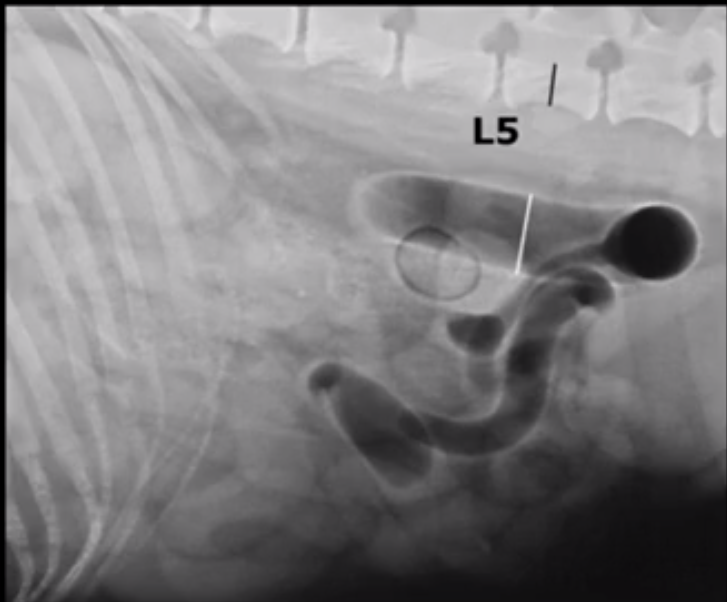

How is focal dilatation of SI defined?

1.6x depth of L5 or 2x rib

What does this image show?

Dilated uterus (no foetuses will be present until day 44)